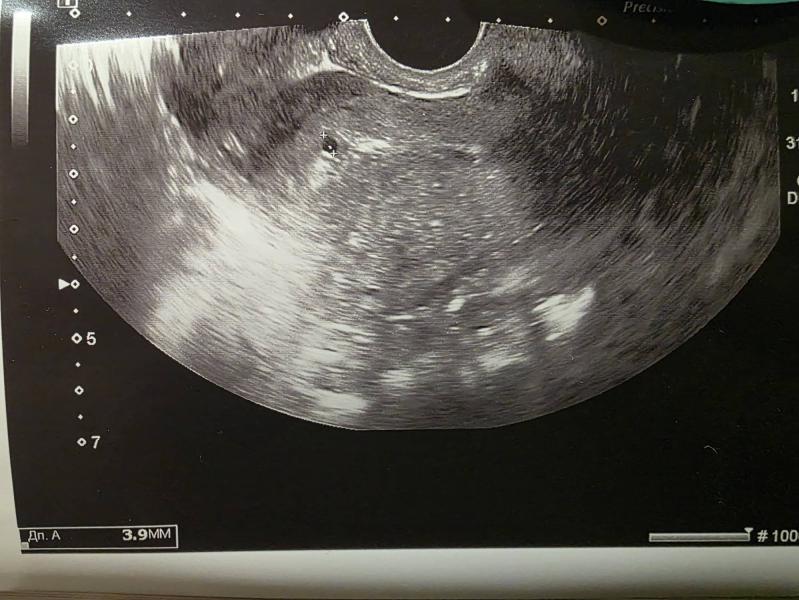

5 недель 1 день

Сегодня познакомились с бусинкой 😁